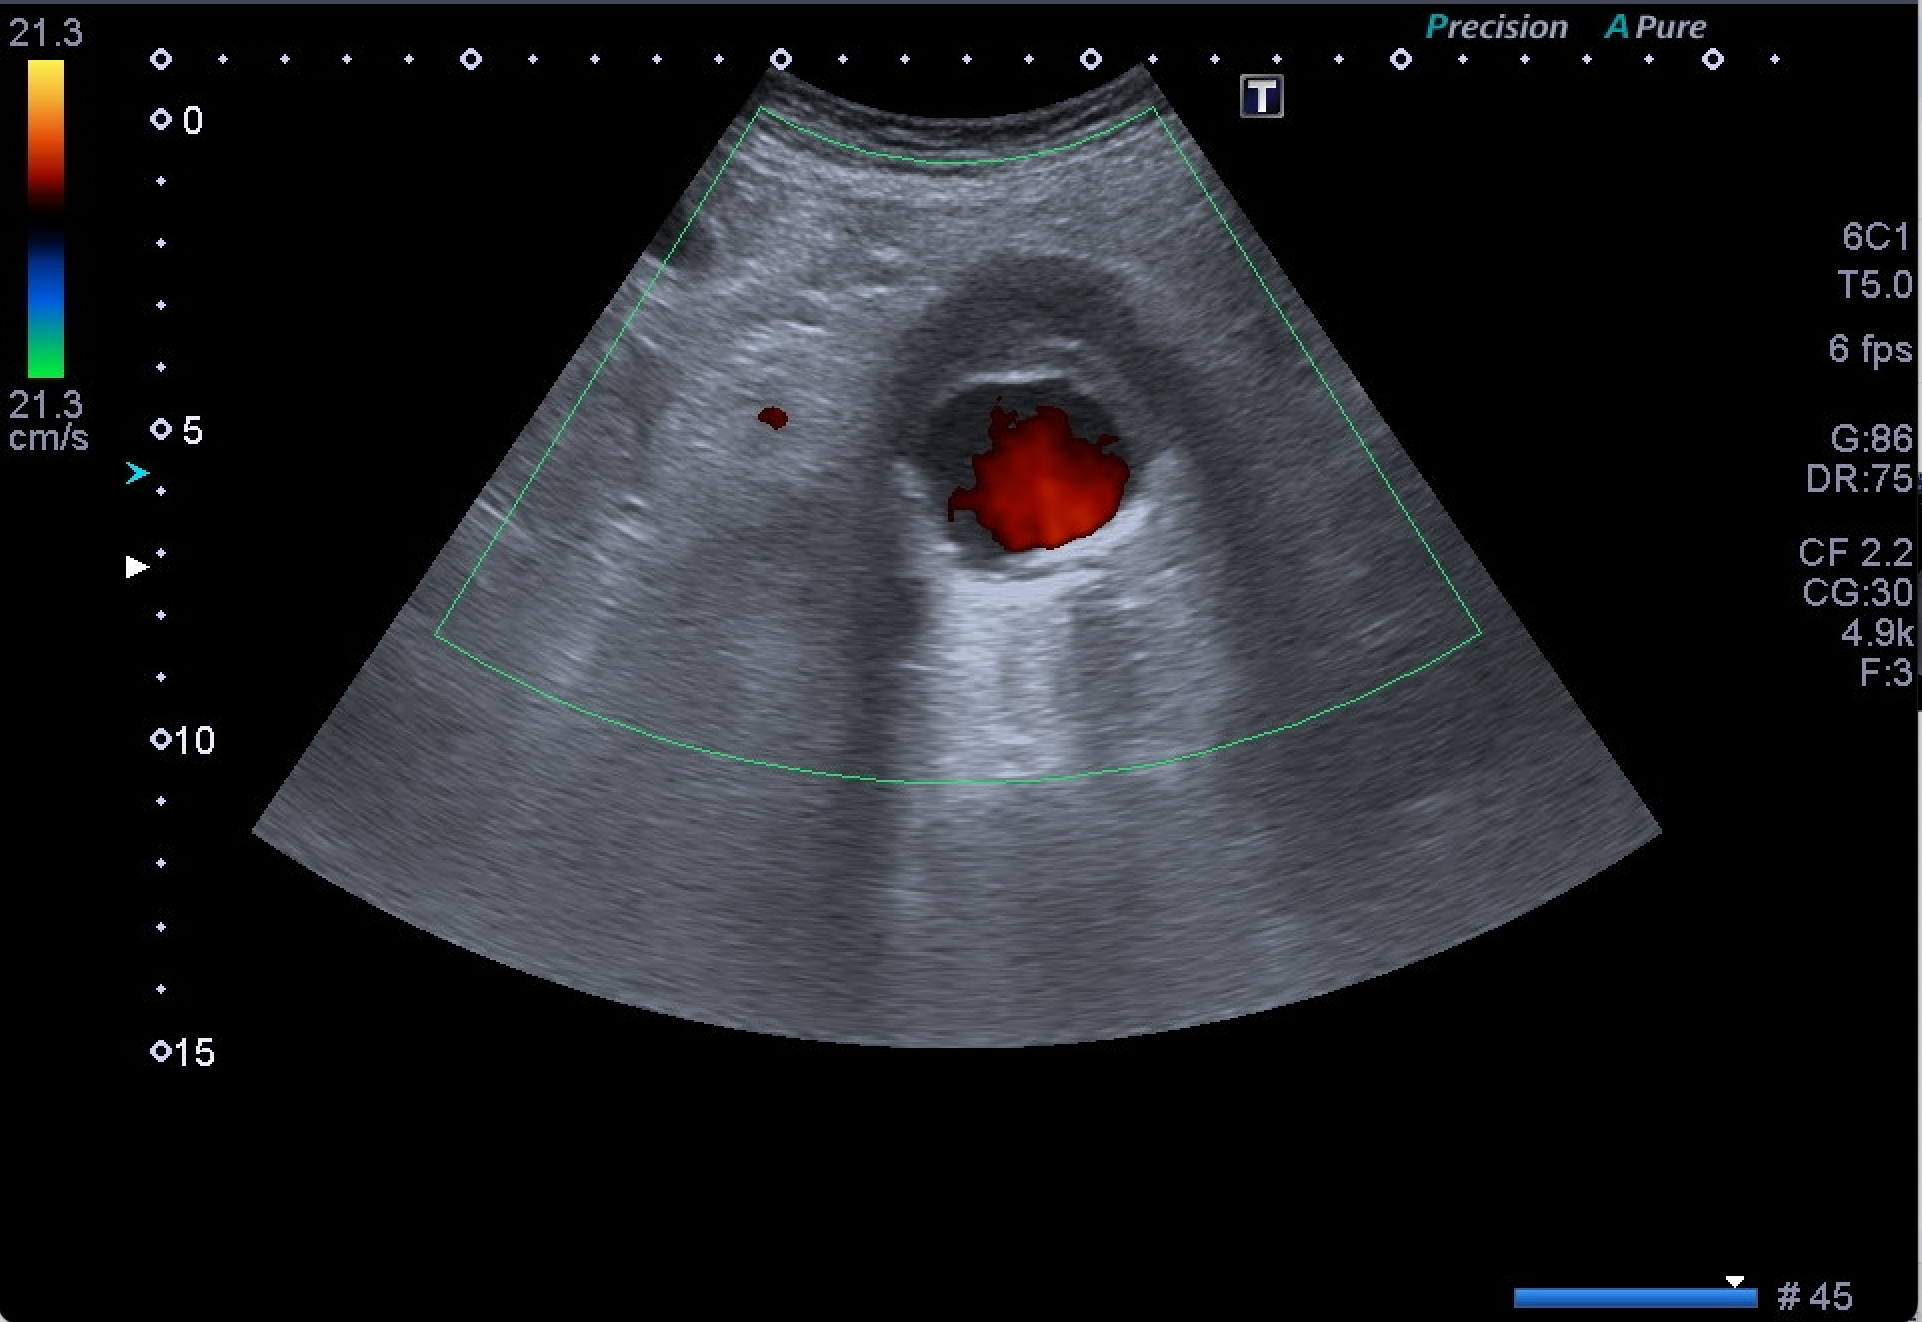

Destaca la visualización de probable litiasis renal derecha, junto con el hallazgo incidental de aneurisma de aorta abdominal, de unos 5,8 cm de diámetro máximo en el plano axial, el cual presenta trombo mural.

Dados los hallazgos, se completa estudio con AngioTC, confirmando la existencia de aneurisma infrarrenal de 6 mm de diámetro mayor, junto con litiasis renal derecha de 5,5 mm y dilatación de la pelvis renal.